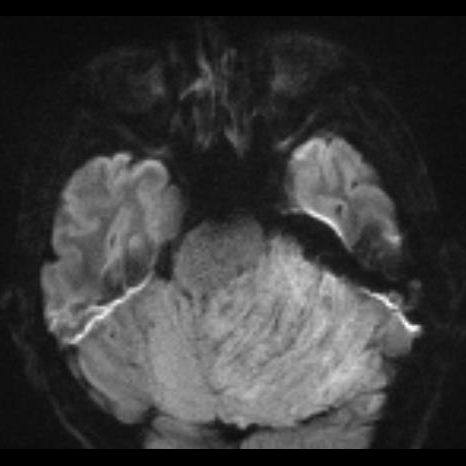

24 yaş, E

Baş ağrısı

Lhermitte-Duclos hastalığı (Dysplastic cerebellar gangliocytoma)